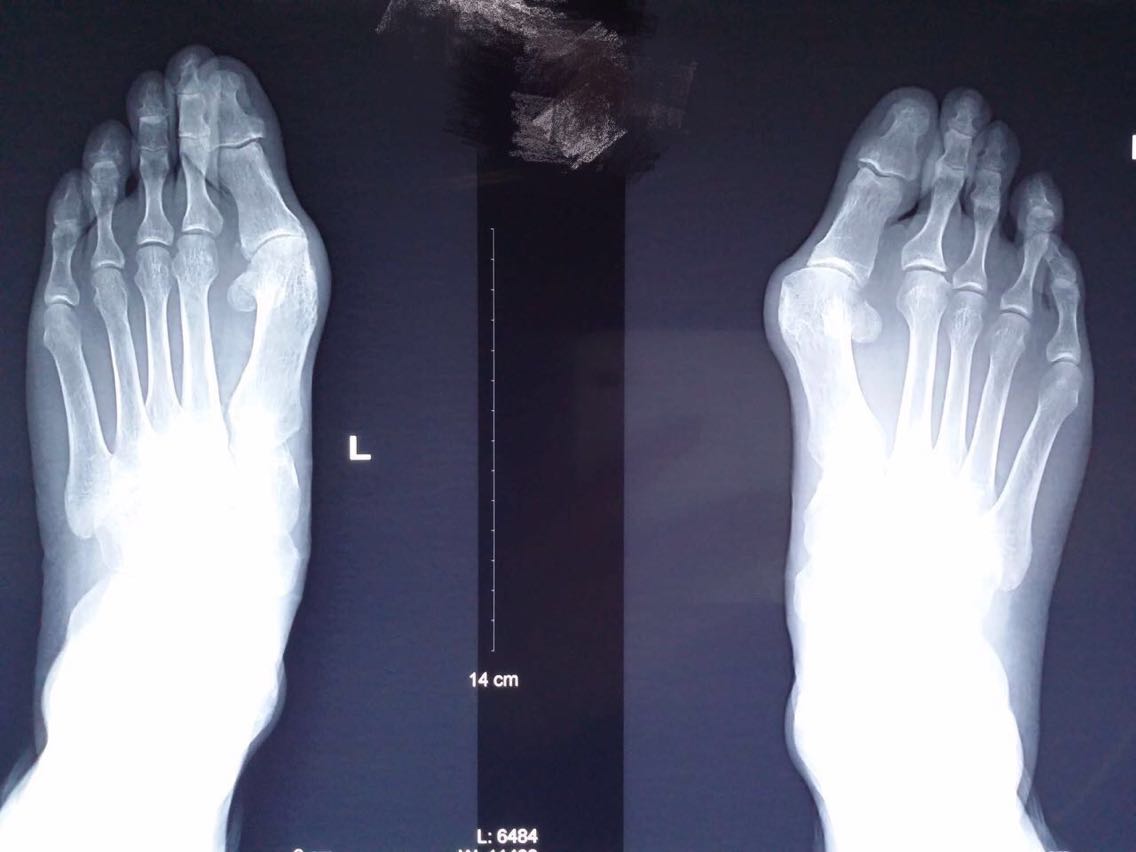

主诉:双足第一趾外翻畸形10余年。 病史:患者F/55,自述双足无明显诱因出现第一趾外翻畸形10余年,长时间行走或工作劳累后出现疼痛,近2年来症状加重。

查体及辅助检查:双足第一趾重度外翻畸形,第一趾长轴与第一跖骨长轴夹角>25°,第一、二跖骨头夹角>9°。

诊断:双足拇外翻畸形 治疗:截骨矫形修复术